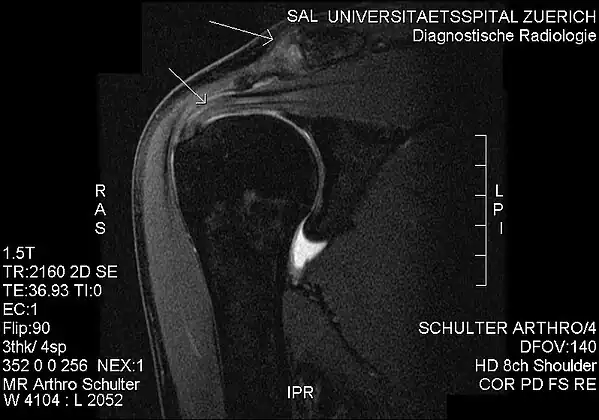

MRI showing subacromial impingement with partial rupture of the supraspinatus tendon, but no retraction or fatty degeneration of the supraspinatus muscle.

Plain x-rays of the shoulder can be used to detect some joint pathology and variations in the bones, including acromioclavicular arthritis, variations in the acromion, and calcification. However, x-rays do not allow visualization of soft tissue and thus hold a low diagnostic value.[2] Ultrasonography, arthrography and MRI can be used to detect rotator cuff muscle pathology. MRI is the best imaging test prior to arthroscopic surgery.[2] Due to lack of understanding of the pathoaetiology, and lack of diagnostic accuracy in the assessment process by many physicians,[18] several opinions are recommended before intervention.